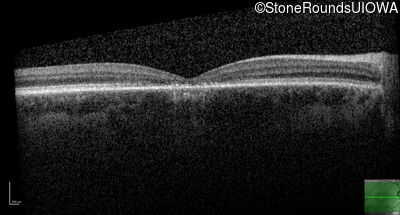

Age at visit: 17 years

OD OS

This 17 year old male was correctable to 20/30 OU when he got his first glasses at age 5. At age 13 his best corrected vision was 20/40 OU. He feels that his color vision has always been poor.